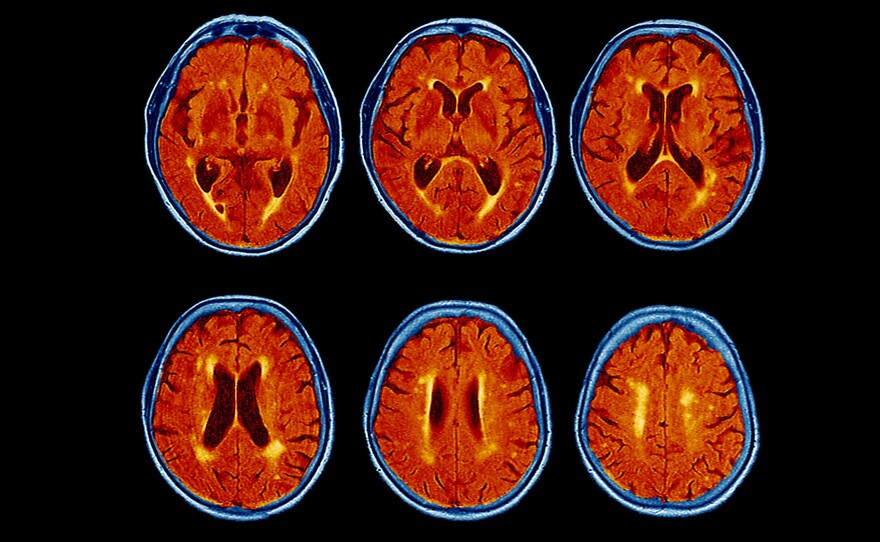

A colored magnetic resonance imaging (MRI) scans of the brain of a 76-year-old patient with dementia shows the brain has atrophied and the dark brown fluid-filled spaces have become enlarged.